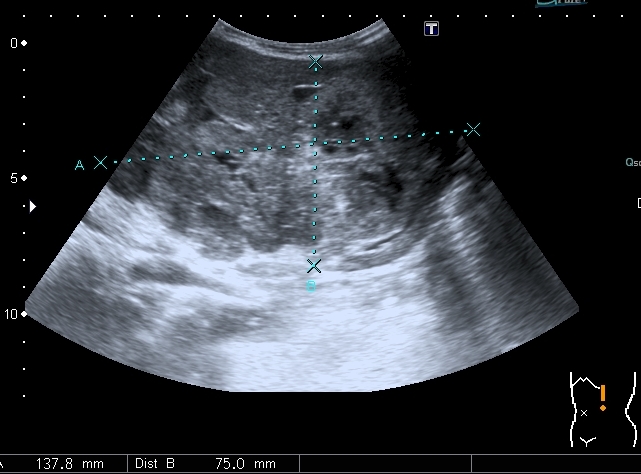

Добавляю источник изменений в легких, печени и забрюшинном пространстве

Всё левое подреберье было выполнено опухолевым конгломератом, источником его я предположил левую почку, хотя разобраться , где почка, селезёнка, а тем более надпочечник я не смог.

По сложившейся тактике при обнаружении опухолевых образований мы не занимаемся морфологической верификацией, а отправляем ребёнка в головное учреждение, наверное это правильно - в лечении детских опухолей иногда бывают важны даже часы. Тем не менее , по УЗИ картине больше данных за нефробластому - есть остатки деформированной собирательной системы в области нижнего полюся образования, там же - немного ткани, похожей на нормальную почечную.

ЦДК образований в лёгких не делал, если быть откровенным, порядок находок у этого пациента был следующим: МТС в печени - изменения в нижней доле правого лёгкого - забрюшиное пространство - левая почка - левое лёгкое - правое лёгкое - рентген лёгких. Картина в комплексе была и так ясна, т.е. то, что это MTS сомнений не вызывало. Ну а после патогномоничной рентгеновской картины - вопросов тем более не было.